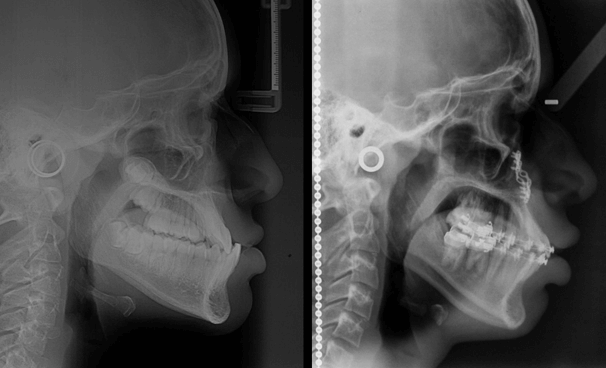

Cefalometría Lateral Inicial

Se realizaron análisis cefalométrico de Ricketts donde se evidencian características como concavidad facial, altura facial disminuida, alteración de la altura facial posterior con el plano Xi por debajo del plano oclusal, Retroinclinación del incisivo superior y Proinclinación y protrusión del incisivo inferior, labio superior corto y en retroquelia y proquelia del labio inferior, prognatismo condilar y prognatismo mandibular, patrón de crecimiento horizontal con tendencia al biotipo braquifacial.